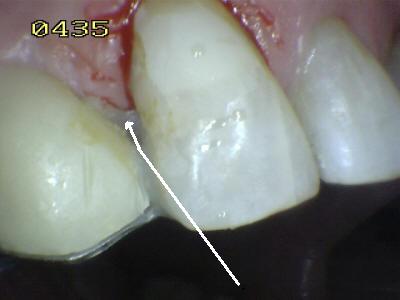

Procedimiento de cementado, se debe tener cuidado de eliminar los excesos de cemento (flechas blancas) antes de su endurecimiento; dado que el espesor de cemento puede ser importante por la desadaptación por caries.